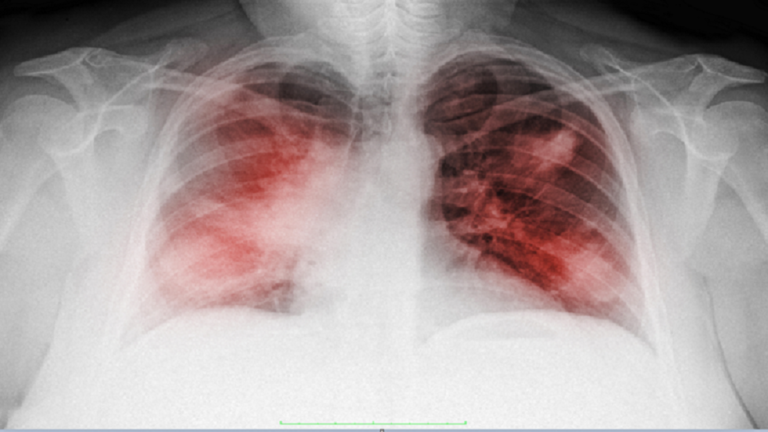

روسيا – أعلن إيفان كاراسيف، أخصائي طب وجراحة الأورام، أن أعراض الالتهاب الرئوي عند الإصابة بـ “كوفيد-19” وسرطان الرئة تتطابق جزئيا، لذلك من السهل الخلط بينها.

وقال، تشمل المضاعفات الصعبة، التهابا رئويا ثنائي الجانب (يلاحظ في 75% من الحالات)، ومتلازمة الضائقة التنفسية الحادة (17%) و متلازمة خلل وظيفة الأعضاء المتعدد (11%).